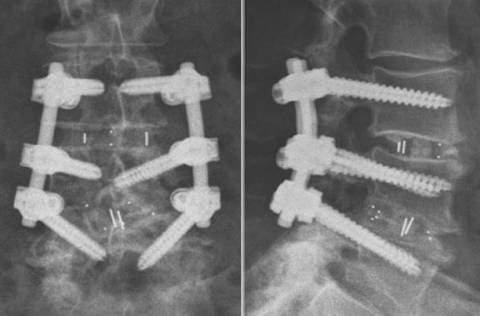

Транспедикулярная система TangoRS L3-L5 и спондилодез кейджами Pezo –T в сегменте L4-L5.

Передний спондилодез кейджами и стабилизация позвоночника системой TangoRS на уровне L2-S1 при дегенеративном сколиозе поясничного отдела позвоночника.